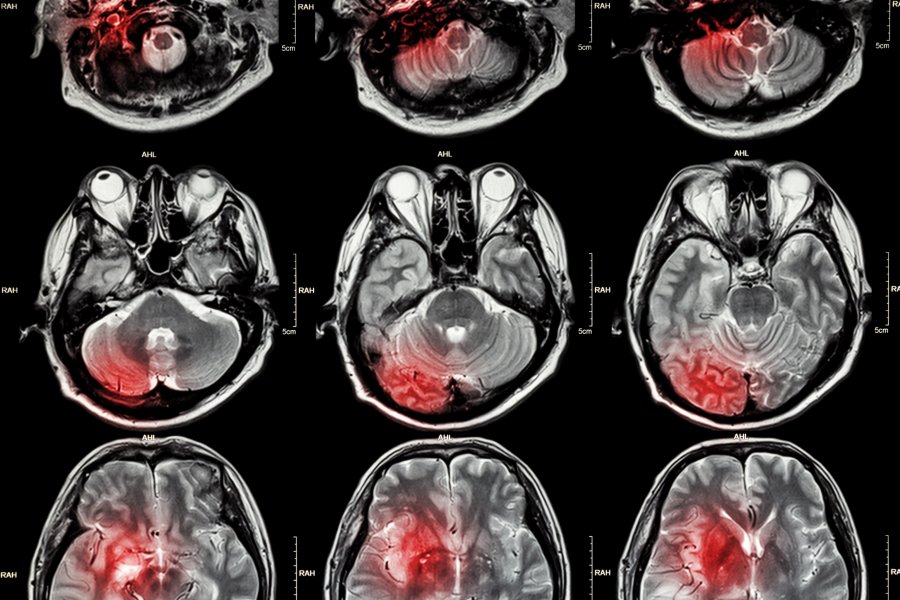

Diagnozę stawia się na podstawie występujących objawów oraz obrazu uzyskanego z rezonansu magnetycznego głowy lub tomografii komputerowej. Badania obrazowe pozwalają ocenić, jaki rodzaj udaru wystąpił u chorego – krwotoczny czy niedokrwienny – co ma znaczenie dla sposoby leczenia. Ważne jest również ustalenie, czy nie doszło do obrzęku mózgu lub innych zmian wymagających natychmiastowych działań leczniczych. Prócz badań obrazowych wykonuje się także badania krwi, echokardiografię oraz USG tętnic szyjnych, aby ustalić przyczynę udaru.